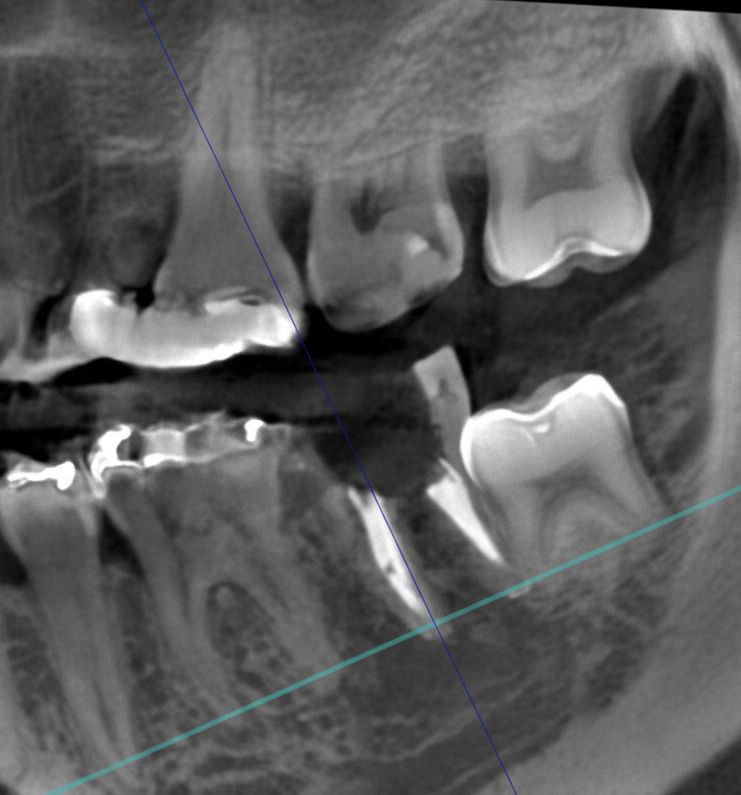

従来のレントゲン画像は平面像(二次元)でしたが、歯科用CT画像は立体画像(三次元)でみることが出来ます。

ですから、インプラントや歯周病などの診断に有効で、従来の平面画像では難しいとされた骨の幅の確認などが行えます。CT撮影で様々な角度から診断することで、正確な診査・診断に役立ち、より安全で確かな治療を行うことが可能となります。

歯の神経や根っこに潜む細菌をきれいに取り除く、根管治療。CT画像では、根の本数や神経の入っている管の方向、そして位置を正確に把握することができます。また、細かい根の破折も発見できるので、早期治療が可能になります。

歯科用CTを親知らずの抜歯に利用することで、神経までの正確な距離や、周囲の炎症の程度、病巣の有無や大きさ、位置なども判断・考慮して、治療を行うことができます。また埋伏歯などの位置なども精密に判断できるので、余分な切開や骨の切削などを避けることができます。